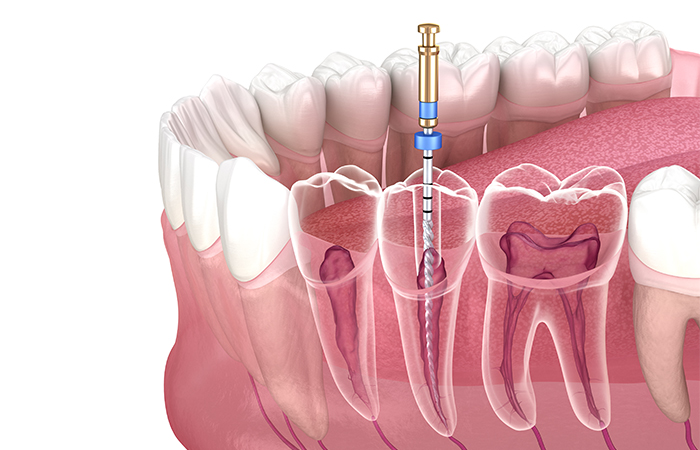

歯の神経を丁寧に

除去します

まず、細菌に汚染された歯の神経や血管を丁寧に取り除きます。

局所麻酔を行ってむし歯を削り、歯の神経があらわれたらファイルという針のような器具を使って神経を除去する治療です。

当院では、唾液に含まれる細菌が患部に入り込むのを防ぐために、ラバーダムといわれる薄いゴム製のシートを使って丁寧に治療を行っています。

根管を拡大し歯の内部を

キレイにします

神経を除去してから空洞になった根管を拡大し、殺菌力の強い薬剤を使用して歯の内部を丁寧に消毒します。根管は複雑な形状をしているため、根管拡大は高度な技術が必要な治療です。

また、汚染された神経が残ると再発の恐れがあるため、感染した歯質などもしっかり取り除きます。

根管の充填を行い、

被せ物をします

根管内を十分に消毒・洗浄したら、細菌が繁殖してむし歯が再発するのを防ぐために、空洞になった根管内に特殊な薬剤でできた根管充填材をすき間なく詰め込みます。